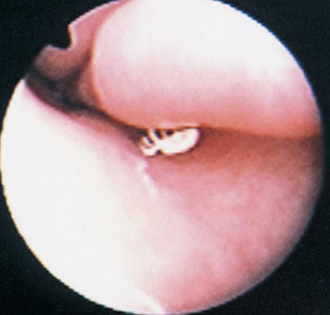

- 작고 하얀 기생충, 약 1mm size.

- 심한 재채기와 코를 비비는 행동.

- 머리를 흔들고, reverse sneezing, 만성 콧물, 코피도 발생 가능.

- 비강 이물에 의한 증상과 유사함.

- 진단 : Rhinoscopy, retrograde nasal flushing - 내시경을 넣고 뒤로 180도 꺾어서 검사.